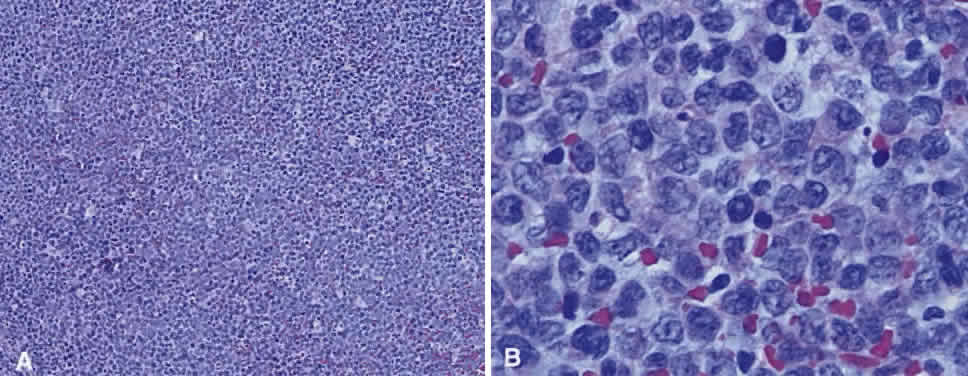

Numerous attempts have been made to classify lymphoid processes for clinical management and prediction of prognosis. Early classifications included only disease localized to the lymph node, which made classification of extranodal disease difficult and inaccurate. The Rappaport classification, first developed in 1956 and then modified in 1978, attempted to categorize lymphomas in two ways, first, using cytologic characteristics identified by conventional stains, and second, distinguishing between the follicular and diffuse growth pattern histologically38,39 (Table 3). The distinction of nodular, or follicular, and diffuse growth was considered useful because of the generally indolent nature of follicular growth, in which the tumor cell aggregates resemble germinal centers and disrupt the normal architecture of the node, compared with the appearance of diffuse growth, in which the lymph node is completely obliterated by a dense monotonous sheet of lymphocytes. In subsequent years, however, it was found that the descriptive growth pattern and cytogenetic characteristics of the Rappaport system did not predict prognosis reliably and were biologically inaccurate. The complexity of correlating degrees of differentiation, mitotic activity, and cytologic characteristics to prognosis have made lymphomas difficult to classify and have led to subsequent systems. The second system, proposed by Lukes-Collins in 1974, classifies lymphoma histologically according to its normal counterpart B-cell, T-cell, or null cell origin40,41 (see Table 3). Histologically, cells may appear small cleaved, large cleaved, small noncleaved, or large noncleaved, depending on the stage of B-cell arrest during normal transformation to immunoblast. Ninety percent of lymphomas are of B-cell origin, and the null cell also usually is of B-cell origin, although 10% may originate from T cells or histiocytes.42,43 Burkitt's lymphoma, the only lymphoma common in children, is a B-cell variant with a background of reactive histiocytes. As a result of histologic classification by Lukes-Collins, 76% of histiocytic lymphomas according to the Rappaport system were found to be not of histiocytic origin but of lymphocytic origin.40,44 The third system, the Working Formulation devised by the National Cancer Institute in 1982, attempted to predict prognosis by grouping lymphoma according to natural history, response to therapy, and overall survival.45 Three broad categories were established in terms of 5-year survival rates, the low-grade with a 50% to 70% survival rate, intermediate with 35% to 45%, and high grade with 23% to 32% (see Table 3). Orbital reactive hyperplasia, a relatively low-grade lesion, can be associated with systemic disease, whereas malignant or high-grade orbital lymphomas may be isolated findings. The Ann Arbor Staging Classification for Hodgkin's and non-Hodgkin's lymphomas was developed to stage disease based on systemic areas of involvement as a means of establishing a baseline for treating disease and following clinical progression46 (Table 4). Histologic classification, however, has been recognized as more useful than localization in the clinical management of nonHodgkin's lymphoma.47

While the Lukes-Collins and Working Formulation classifications were in wide use in the United States, the European literature made references to the Kiel and updated Kiel classifications, which led to disparities in classifying lymphoma. Another classification proposed by Jakobiec and coworkers was the most comprehensive classification available for orbital disease but failed to integrate systemic lymphoma, which is known to be associated in approximately half of cases.1 The most recent classification has made the system universal, comprehensive, and useful to interdisciplinary teams that characteristically manage patients with lymphoma. The International Lymphoma Study Group in 1994 developed the Revised European-American Lymphoma (REAL) classification (Table 5), which classifies lymphoid disease by the cell of origin into B-cell, T-cell, and natural killer cell lymphomas, leukemias, myeloma, and variants of Hodgkin's disease26 (Fig. 4). The identification of the putative benign progenitor cells has been inferred through the use of cell marker studies. The results of molecular genetic studies to identify immunoglobulin gene rearrangements and cytogenetic studies to detect chromosomal translocations in monoclonal proliferations have also been incorporated. A significant contribution of the REAL classification has been to incorporate primary extranodal lymphomas as recognizable and classifiable entities. As a result, new variants in this list include lymphoplasmacytic lymphoma, mantle cell lymphoma, marginal zone B-cell lymphoma, particularly mucosal-associated lymphoid tissue (MALT) lymphoma, subclasses of large cell lymphoma, and the natural killer cell lymphomas. Comparisons of the REAL classification to the Working Formulation and the Kiel classification are shown in Tables 6 and 7, respectively.48 The first series of 112 orbital lymphomas using the REAL classification reported the accuracy and utility of the system in classifying orbital lesions and predicting prognosis in combination with currently available immunophenotyping and immunocytogenetic studies.49 The REAL classification does not classify disease based on the degree of differentiation or clinical prognosis. However, a proposed prognostic scheme has been developed in accordance with the REAL classification28 (Table 8). In this text, tumor nomenclature adheres as strictly as possible to the REAL classification.